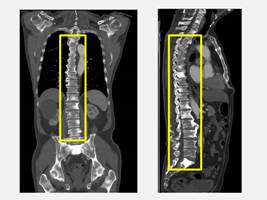

70歲的余先生最近幾個月來因背痛嚴重影響生活品質,自以為只是年紀大造成的脊椎退化或筋骨痠痛,靠止痛藥和熱敷就能緩解,因此沒有積極就醫。余先生一直到子女堅持陪同參加仁愛長庚合作聯盟醫院(大里仁愛醫院)的例行健康檢查時,竟意外發現攝護腺特異抗原(PSA)與鹼性磷酸(ALK-P)指數明顯異常。健康管理中心醫師敏銳察覺可能是罹患攝護腺癌且轉移,立即安排影像學檢查與轉介至泌尿科劉緯陽主任門診,進一步檢查後確診為攝護腺癌合併瀰漫性骨轉移。幸好透過跨科合作及早確認病因,余先生已展開治療,目前病情獲得控制。

劉緯陽主任指出,攝護腺癌是台灣男性常見癌症,根據衛福部統計,發生率在男性癌症中排名前幾位。早期攝護腺癌通常沒有明顯症狀,許多患者常因為排尿困難、夜尿頻繁、血尿,甚至像余先生一樣出現骨痛才就醫,往往病情已屬晚期。余先生因背痛接受健檢而發現異常,算是「因禍得福」,否則若再拖延,可能導致骨折、神經壓迫等嚴重併發症。

針對攝護腺癌骨轉移的治療,劉緯陽主任指出,目前主要以荷爾蒙治療(男性荷爾蒙抑制)作為第一線,搭配新一代標靶荷爾蒙藥物或化學治療,可有效延緩病程。同時也會針對骨轉移給予骨保護治療藥物,或利用放射治療緩解骨痛,提升生活品質。雖然骨轉移代表病程已進入晚期,但若積極治療,病人仍能維持一定存活期與生活功能。